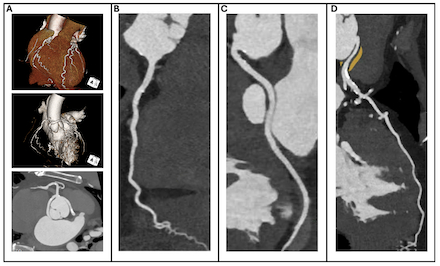

Case: A 65-year-old man with a history of carpal tunnel syndrome, hypertension, and CAA presented with exertional dyspnea. Family history included a brother with hypertrophic cardiomyopathy. Stress testing noted ischemia in the left anterior descending (LAD) and left circumflex (LCX) territories. Invasive angiography and cardiac computed tomography (CT) confirmed an anomalous LAD arising from the right coronary cusp with an interarterial course and a retroaortic LCX arising from the ostium of the right coronary artery without obstructive disease (Figure 1). Echocardiography revealed concentric LV thickening, severe diastolic dysfunction, an apical sparing strain pattern, and dynamic left ventricular outflow tract obstruction (Figure 2). Light-chain amyloidosis was excluded, and cardiac scintigraphy confirmed ATTR-CA (Figure 3). Genetic testing revealed a rare TTR variant of previously uncertain significance (p.Val113Leu), prompting cascade screening.